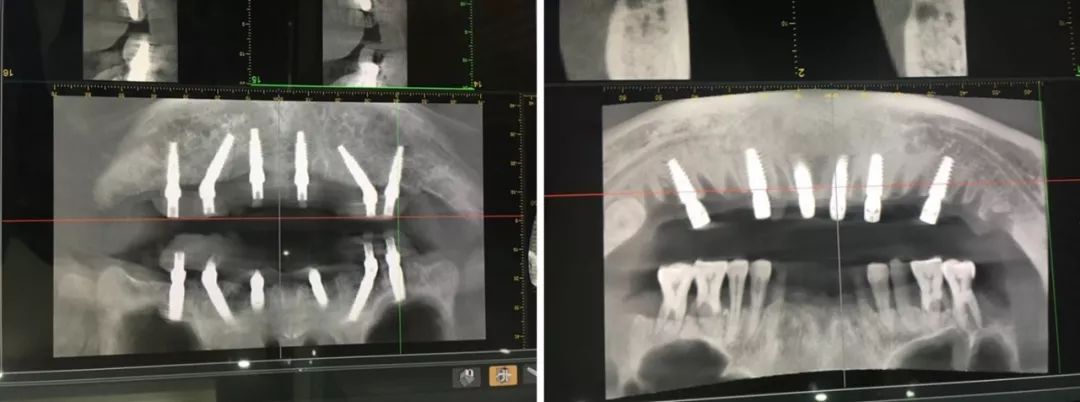

日照口腔医院种植中心配置先进的种植手术室,为患者提供各种类型的种植义齿修复,采用先进的医疗技术装备和种植系统,配备有丹麦3shape口内扫描仪、Yoshida激光治疗仪、卡瓦(KaVo)锥形束CT、超声骨刀等国际先进仪器和设备,装备有瑞士士卓曼等多套国际种植系统,同时配备设备先进的现代化消毒供应室,为疑难复杂病例的诊治提供了必要条件。

医院开展CAD/CAM数字化种植导板技术,通过整合数字化影像、cbct 数据以及数字化加工技术的新型种植导板,充分考虑到了颌骨条件、口腔解剖结构以及修复效果的结合,用以提高手术精度,降低手术风险,减轻患者痛苦。

为让患者在家门口就能够享受高水准专家口腔种植诊疗服务,日照口腔医院种植会诊中心聘请青岛市口腔医疗集团青岛新都口腔医院种植院长张立卫进驻坐诊,平均每年为1000余例牙齿缺失患者带来福音,真正的“技术”流!

医院成立多学科联合种植诊疗平台,由日照口腔医院颌面外一科、颌面外二科及口腔修复科联合成立,强强联合,突破种植专业的局限,依赖各学科知识,全面考虑病情,制定合理的治疗方案,最大程度保障患者的健康利益。